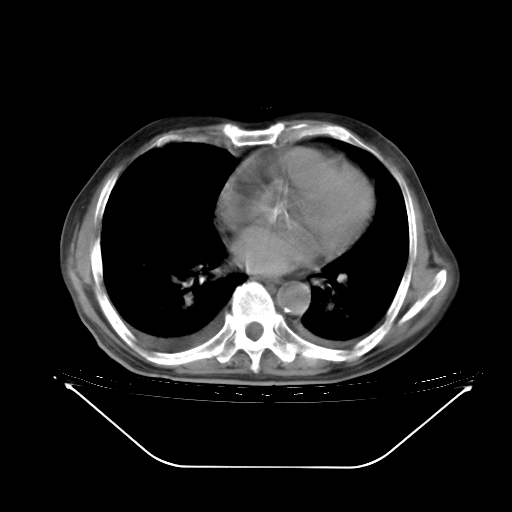

今天复查肺部CT,发现双肺广泛磨玻璃样改变。所以我把3月19日和5月9日相隔50天的肺部CT上传。请大家会诊。

5月9日肺部CT(在4月27日齐鲁医院肺部CT描述部分肺组织磨玻璃样改变,12天后肺组织广泛磨玻璃样改变)

大致读了系列胸部CT:纵隔窗无明显异常,肺窗:从4、27至今:主要是双肺中下野外带可见毛玻璃样改变,目前处于急性肺泡炎阶段,至于原因考虑1、结替组织或胶原血管性疾病所致?2、恶性疾病如恶组在肺部所致的表现或细支气管肺泡癌?3、药物或其它原因如肺蛋白沉着症所致肺泡炎目前不太可能?总之,明天就去请我院的呼吸科、感染科、血液科和临免专家会诊哈。